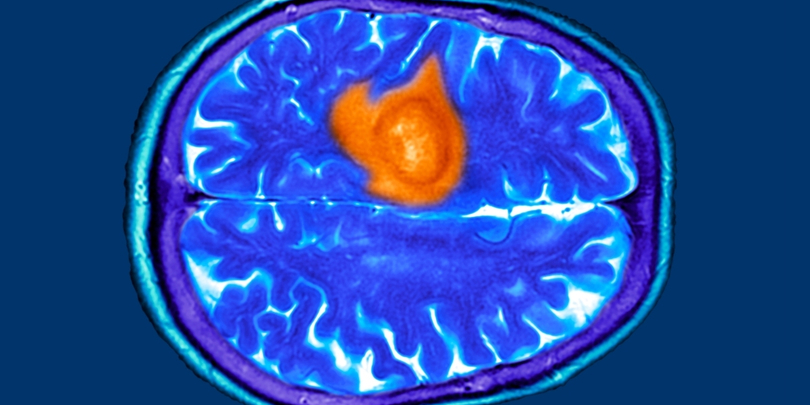

სიმსივნეს ვერაგ დაავადებად მხოლოდ იმიტომ არ მოიხსენიებენ, რომ მაღალი სიკვდილიანობა ახასიათებს. ის საშიშია იმის გამოც, რომ თავს ძალიან გვიან ავლენს, მანამდე კი პაციენტების ორგანიზმში ძირითადად შეუმჩნევლად იზრდება და ვითარდება.

ეს ეხება ტვინის კიბოსაც, რომლის პირველი სიმპტომებიც შეიძლება მარტივად გამოგრჩეთ. ადრეული ონკოლოგიური დიაგნოსტირების სპეციალისტი, ლაურა სტენდენი, თავის გამოცდილებაზე საუბრისას აღნიშნავს, რომ მის პაციენტებში საგანგაშო ნიშნების ვერდაფიქსირება საკმაოდ გავრცელებულია. ვინაიდან დაავადებული ადამიანები სხეულის ასეთ სიგნალებს ყურადღებას არ აქცევენ, მათთვის დიაგნოზის დასმა ზოგჯერ დაგვიანებულია.